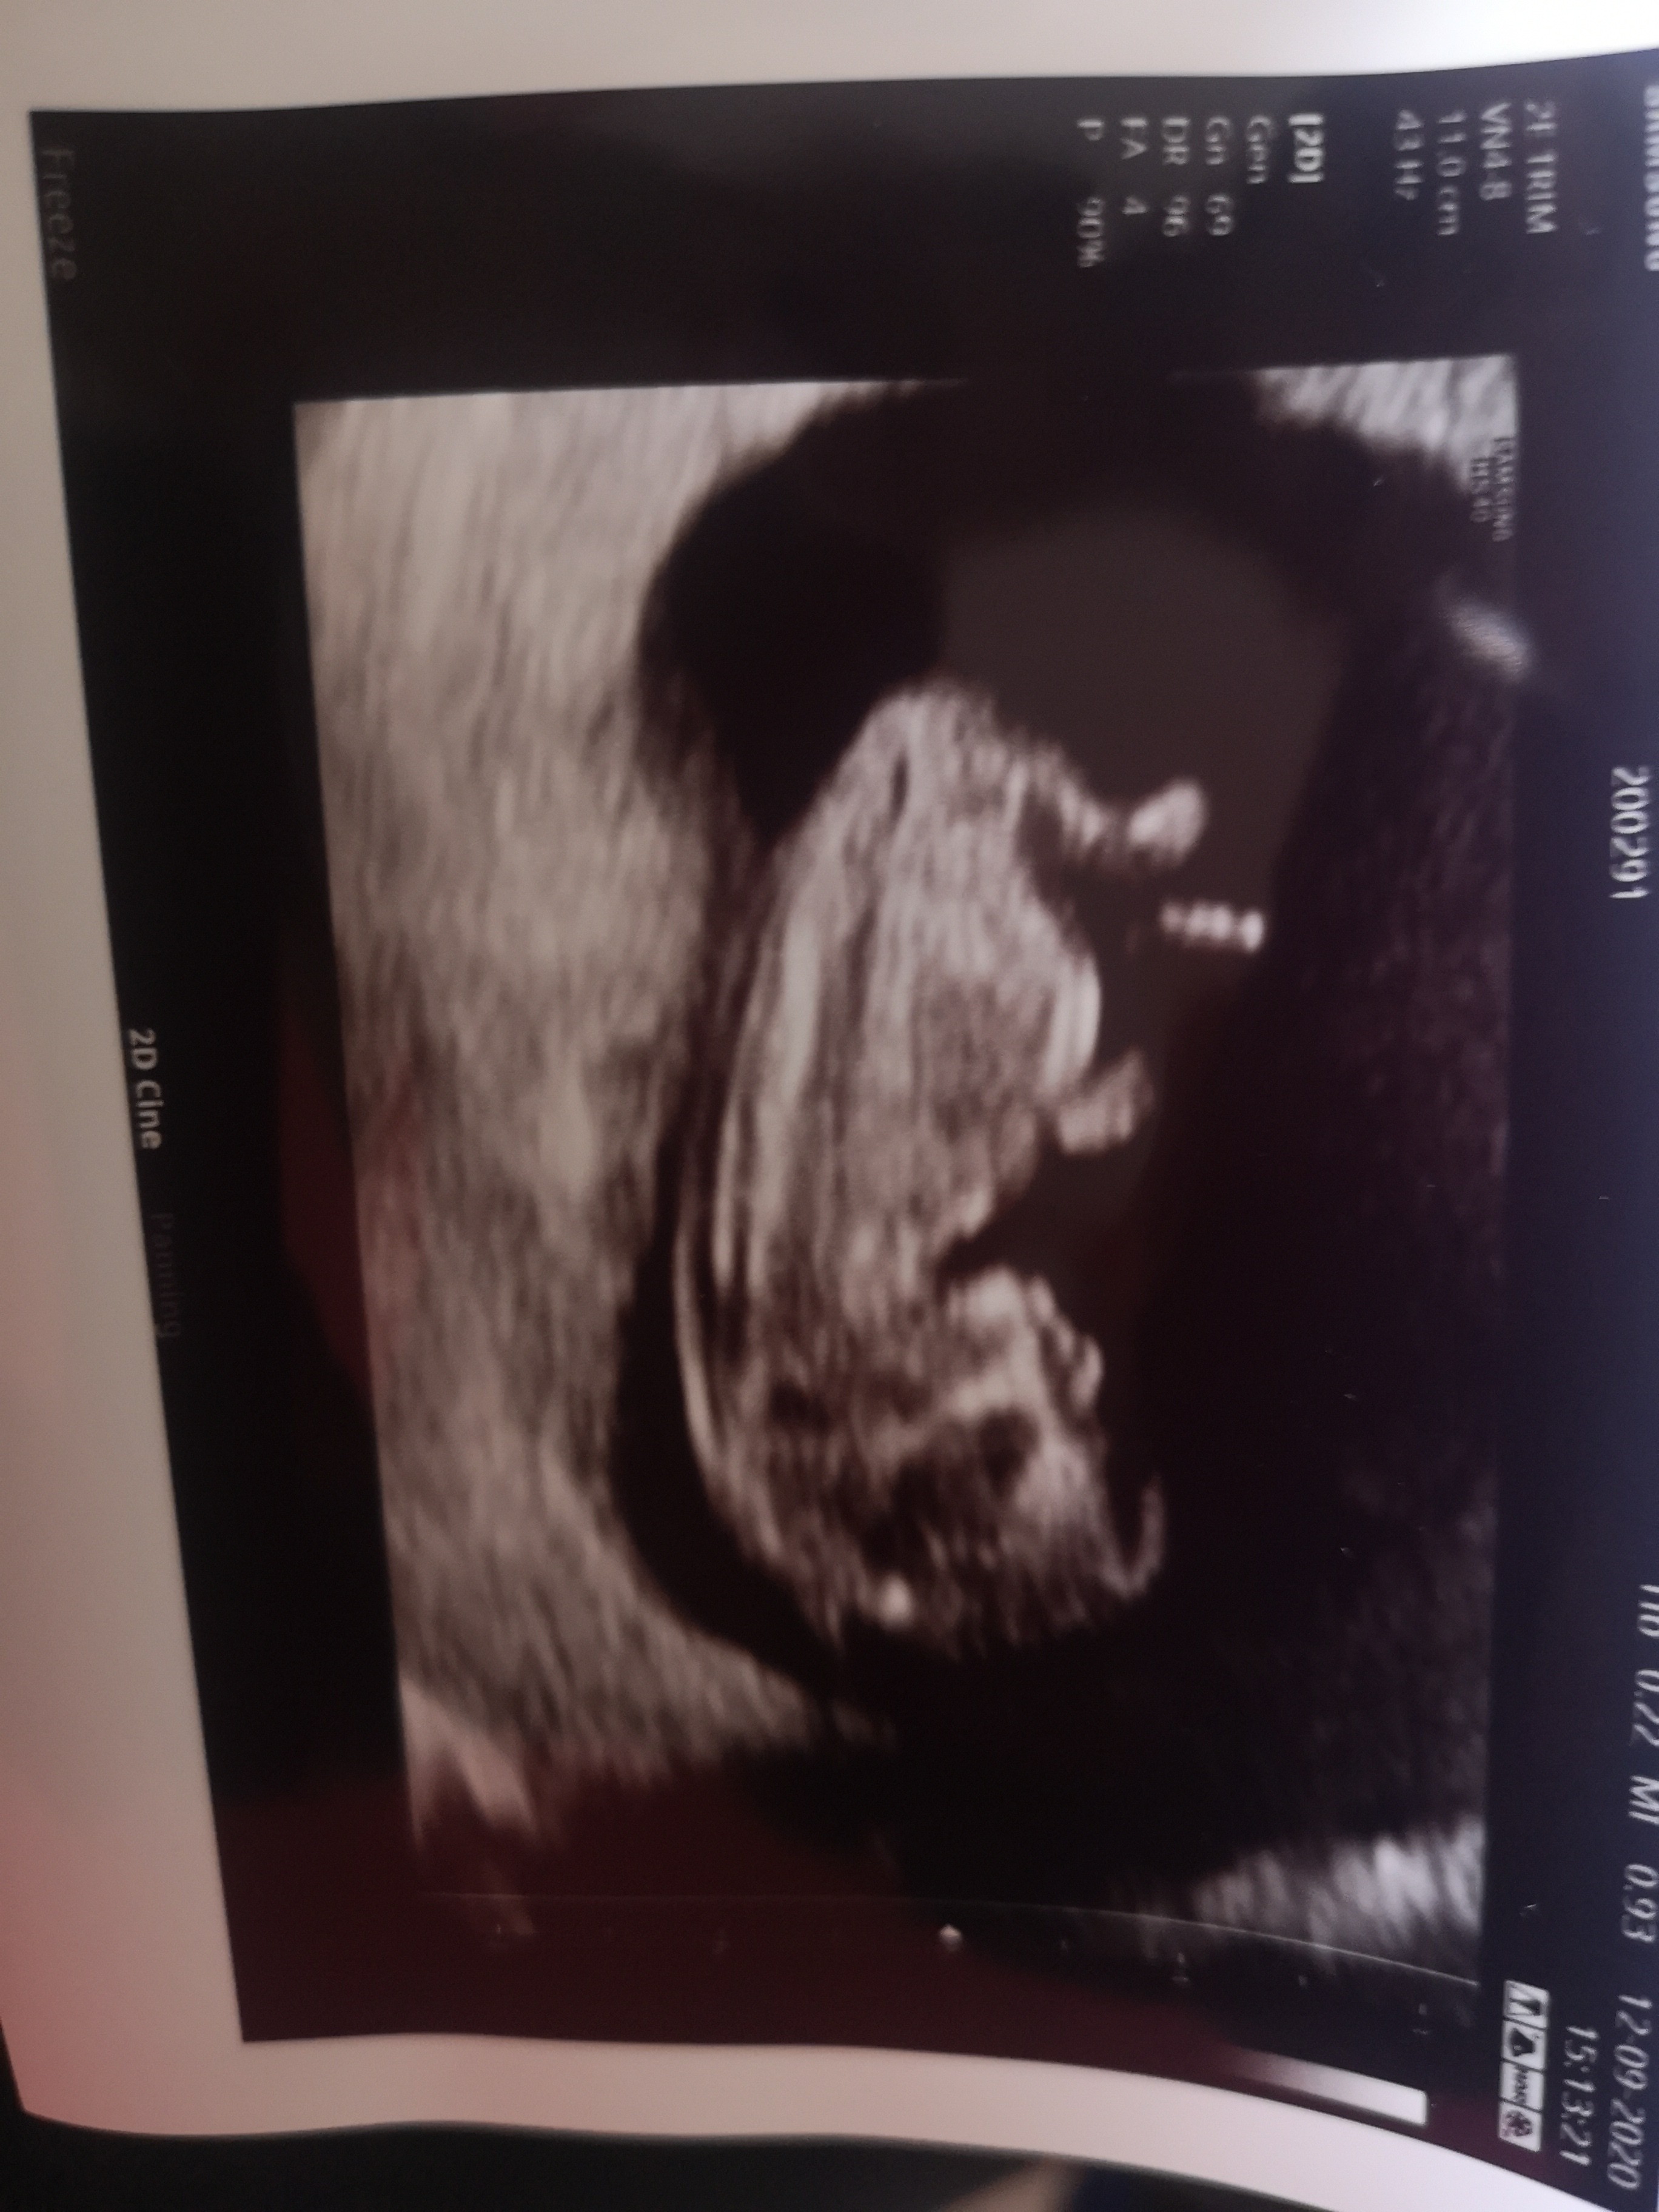

A gdzie jest ten nub a u mnie widzisz?

Załączniki

• IMG_20200912_161732.jpg

IMG_20200912_161732.jpg

1,1 MB · Wyświetleń: 72